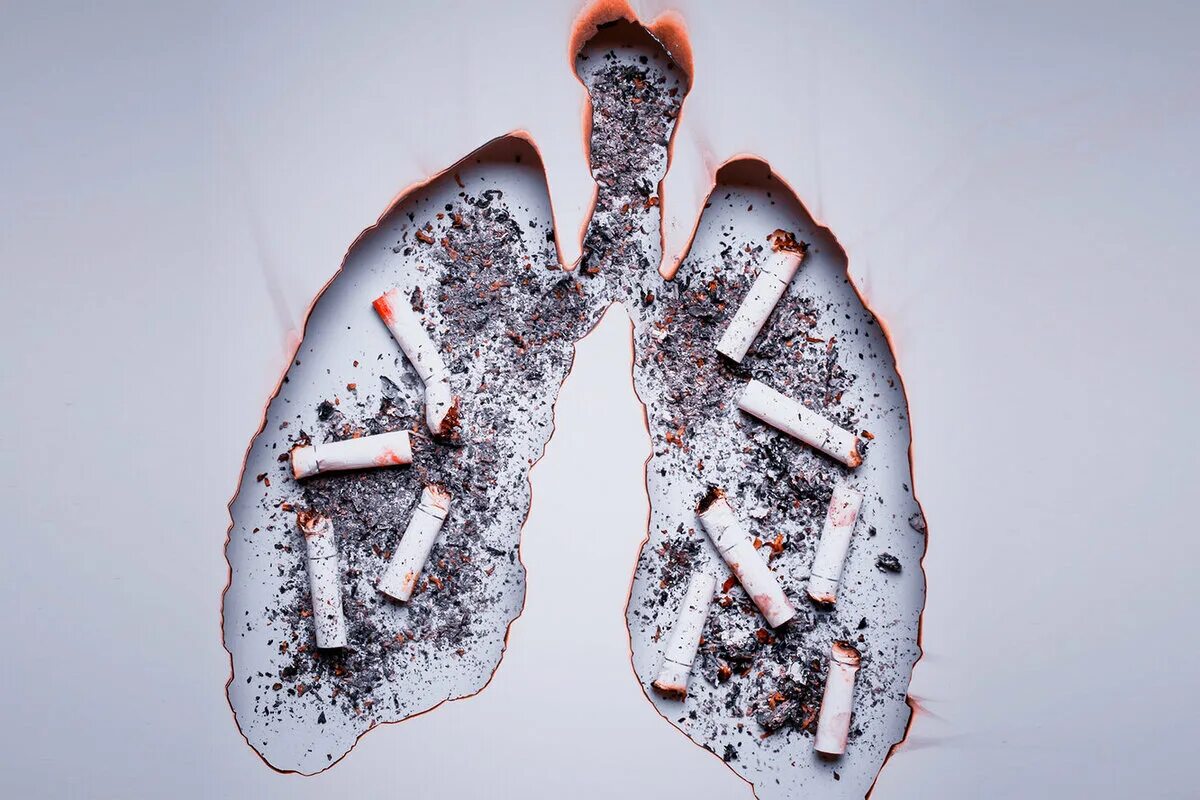

Снимок курильщика